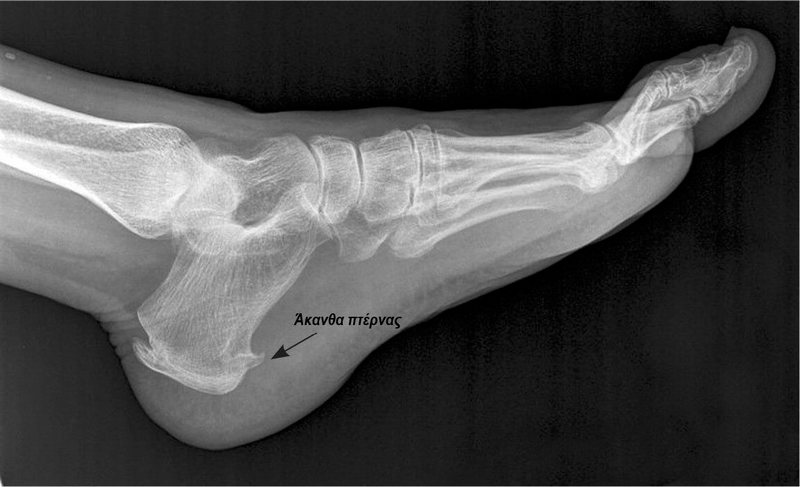

Αυτό θα τον οδηγήσει στον ορθοπαιδικό χειρουργό, ο οποίος με κλινική εξέταση και μια απλή ακτινογραφία, θα διαγνώσει την πελματιαία απονευρωσίτιδα, δηλαδή την ύπαρξη φλεγμονής στην πελματιαία απονεύρωση, ενώ παράλληλα θα εντοπίσει τυχόν συνοδές παθήσεις (σύνδρομο ταρσιαίου σωλήνα, ανεπάρκεια του οπίσθιου κνημιαίου, βραχύς αχίλλειος τένοντας) και θα αποκλείσει άλλες πιθανές αιτίες του πόνου, όπως η οσφυοϊσχιαλγία, η αρθρίτιδα, κάποιο κάταγμα ή οίδημα του οστού της πτέρνας κ.ά.

Πολλές φορές στην ακτινογραφία εντοπίζεται και η ύπαρξη άκανθας πτέρνας, η οποία είναι ένα οστεόφυτο - μια οστέινη ουσιαστικά ανάπτυξη ή προέκταση του οστού της πτέρνας στο κάτω μέρος του - το οποίο ο ασθενής μπορεί να το νιώθει κάποιες φορές σαν “καρφί” που πιέζει τα νεύρα στην περιοχή προκαλώντας πόνο. Η άκανθα πτέρνας λανθασμένα συνδεόταν για χρόνια με την πελματιαία απονευρωσίτιδα, αφού μόνο το 5% όσων έχουν άκανθα εμφανίζουν συμπτώματα πελματιαίας απονευρωσίτιδας. Η άκανθα πτέρνας δεν είναι το αίτιο της απονευρωσίτιδας αλλά το αποτέλεσμα χρόνιων τραυματισμών της πελματιαίας απονεύρωσης.